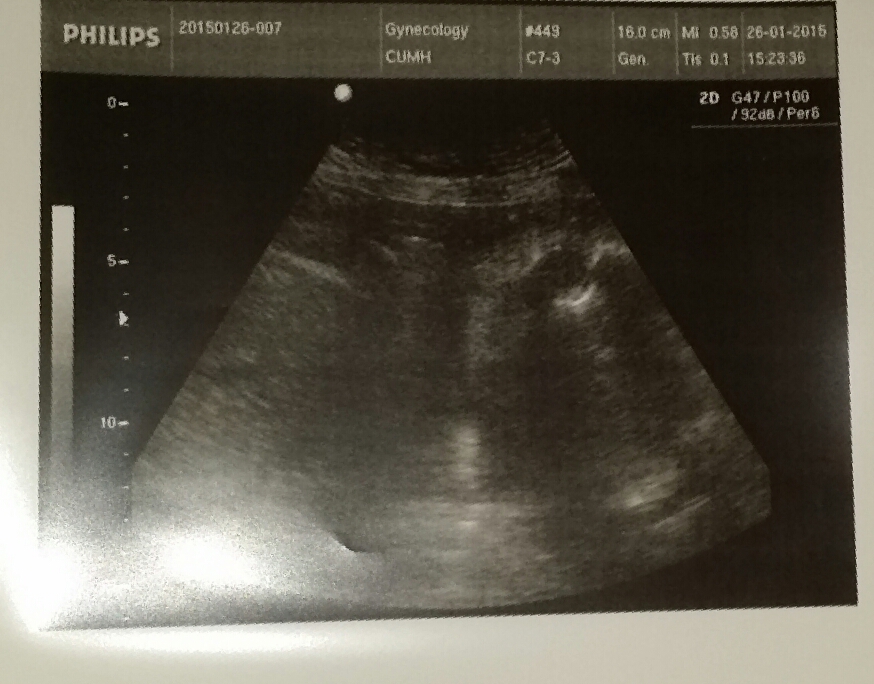

I went for a 4d scan at 16 weeks. She confirmed 100% boy. Went for 30 week scan today being told it's a girl. Can ye take a look at my 4d scan pictures and take a guess please. Everything I have bought is for a boy! A bit devastated at the minute.

Thanks.